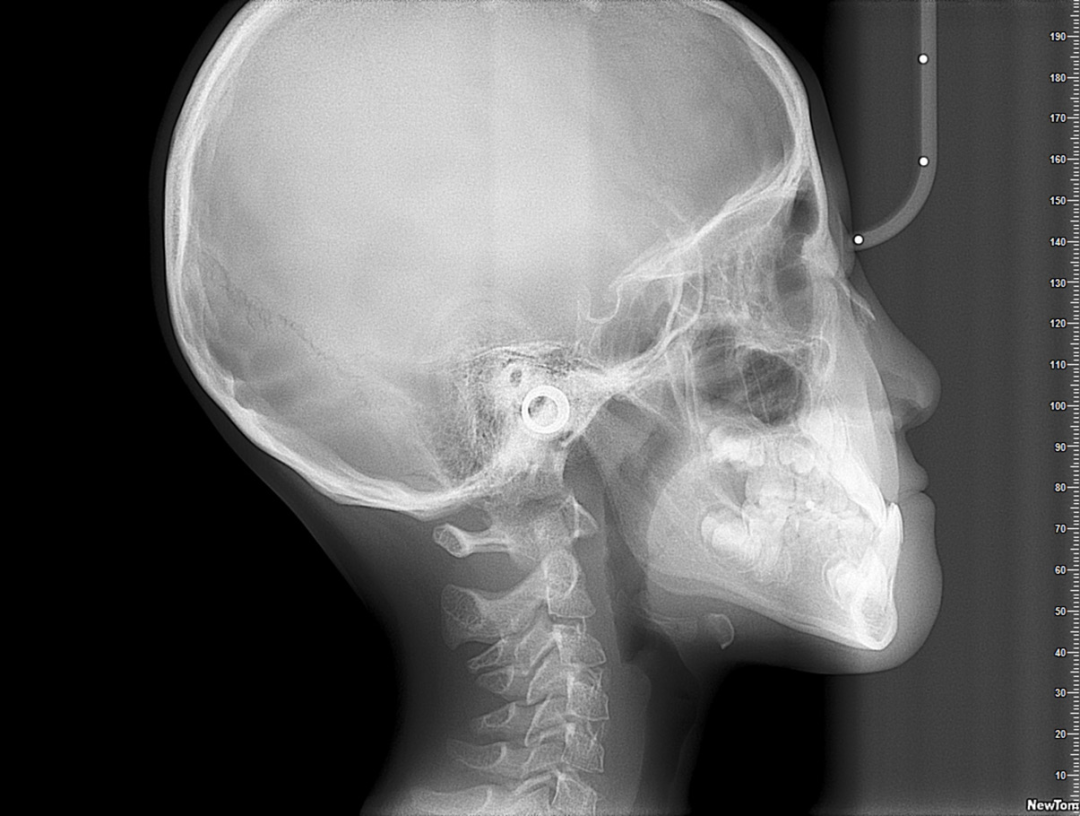

对于一些牙齿咬合、不良习惯以及颌骨发育导致面型美观问题,早期矫正可以取得事半功倍的效果。反颌(地包天)是正畸中的一个“急诊”的问题,发现孩子出现反颌的问题就应该做矫正干预。

反颌如果不做会发生什么呢?大量的研究表明,反颌如果不做矫正干预,上颌骨发育不足不会变差,但也不会变好。

但是下颌骨问题不管的话,以前可能只是上颌发育不足,下颌并不凸,时间久了下颌自然就会越来越前凸,不前凸的也凸,凸的会变得更凸。

因此反颌一定是在5岁左右必须要去完成的,通常通过活动矫治器或者Grace个性化定制硅胶牙套,通常在3-6个月就可以有明显的变化。